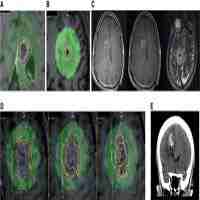

| Abstract | This study aimed to compare MR thermal mapping during laser-induced interstitial thermal therapy (LITT) to thermal lesions observed macroscopically, in order to estimate the 3D size of the coagulative necrosis. Laser irradiation was performed ex-vivo with a 980 nm laser in pig liver in a open low-magnetic field (0.2 T) scanner. The laser light was transmitted through a 1040/600 mum (outer/core diameter) bare-tip silica fiber. The laser energy was applied on a pulsed mode (10 s laser-on, 10 s laser-off) for 12 minutes, power: 6 W, energy: 2160 J. MR thermal mapping used T1 method for its simplicity and its efficiency at low magnetic field. |